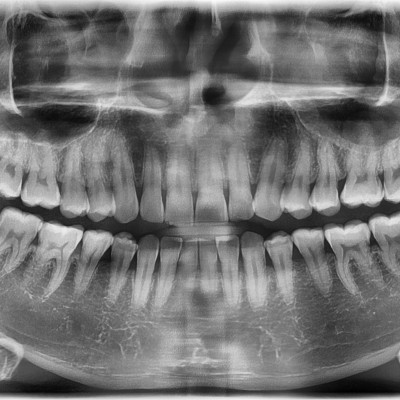

#18,28,38,48 사랑니 발치 #18,28,38,48 사랑니 발치 구강외과 전문의가 당일 발치했습니다.

작성자 이턱이 작성일 01-19 조회 36